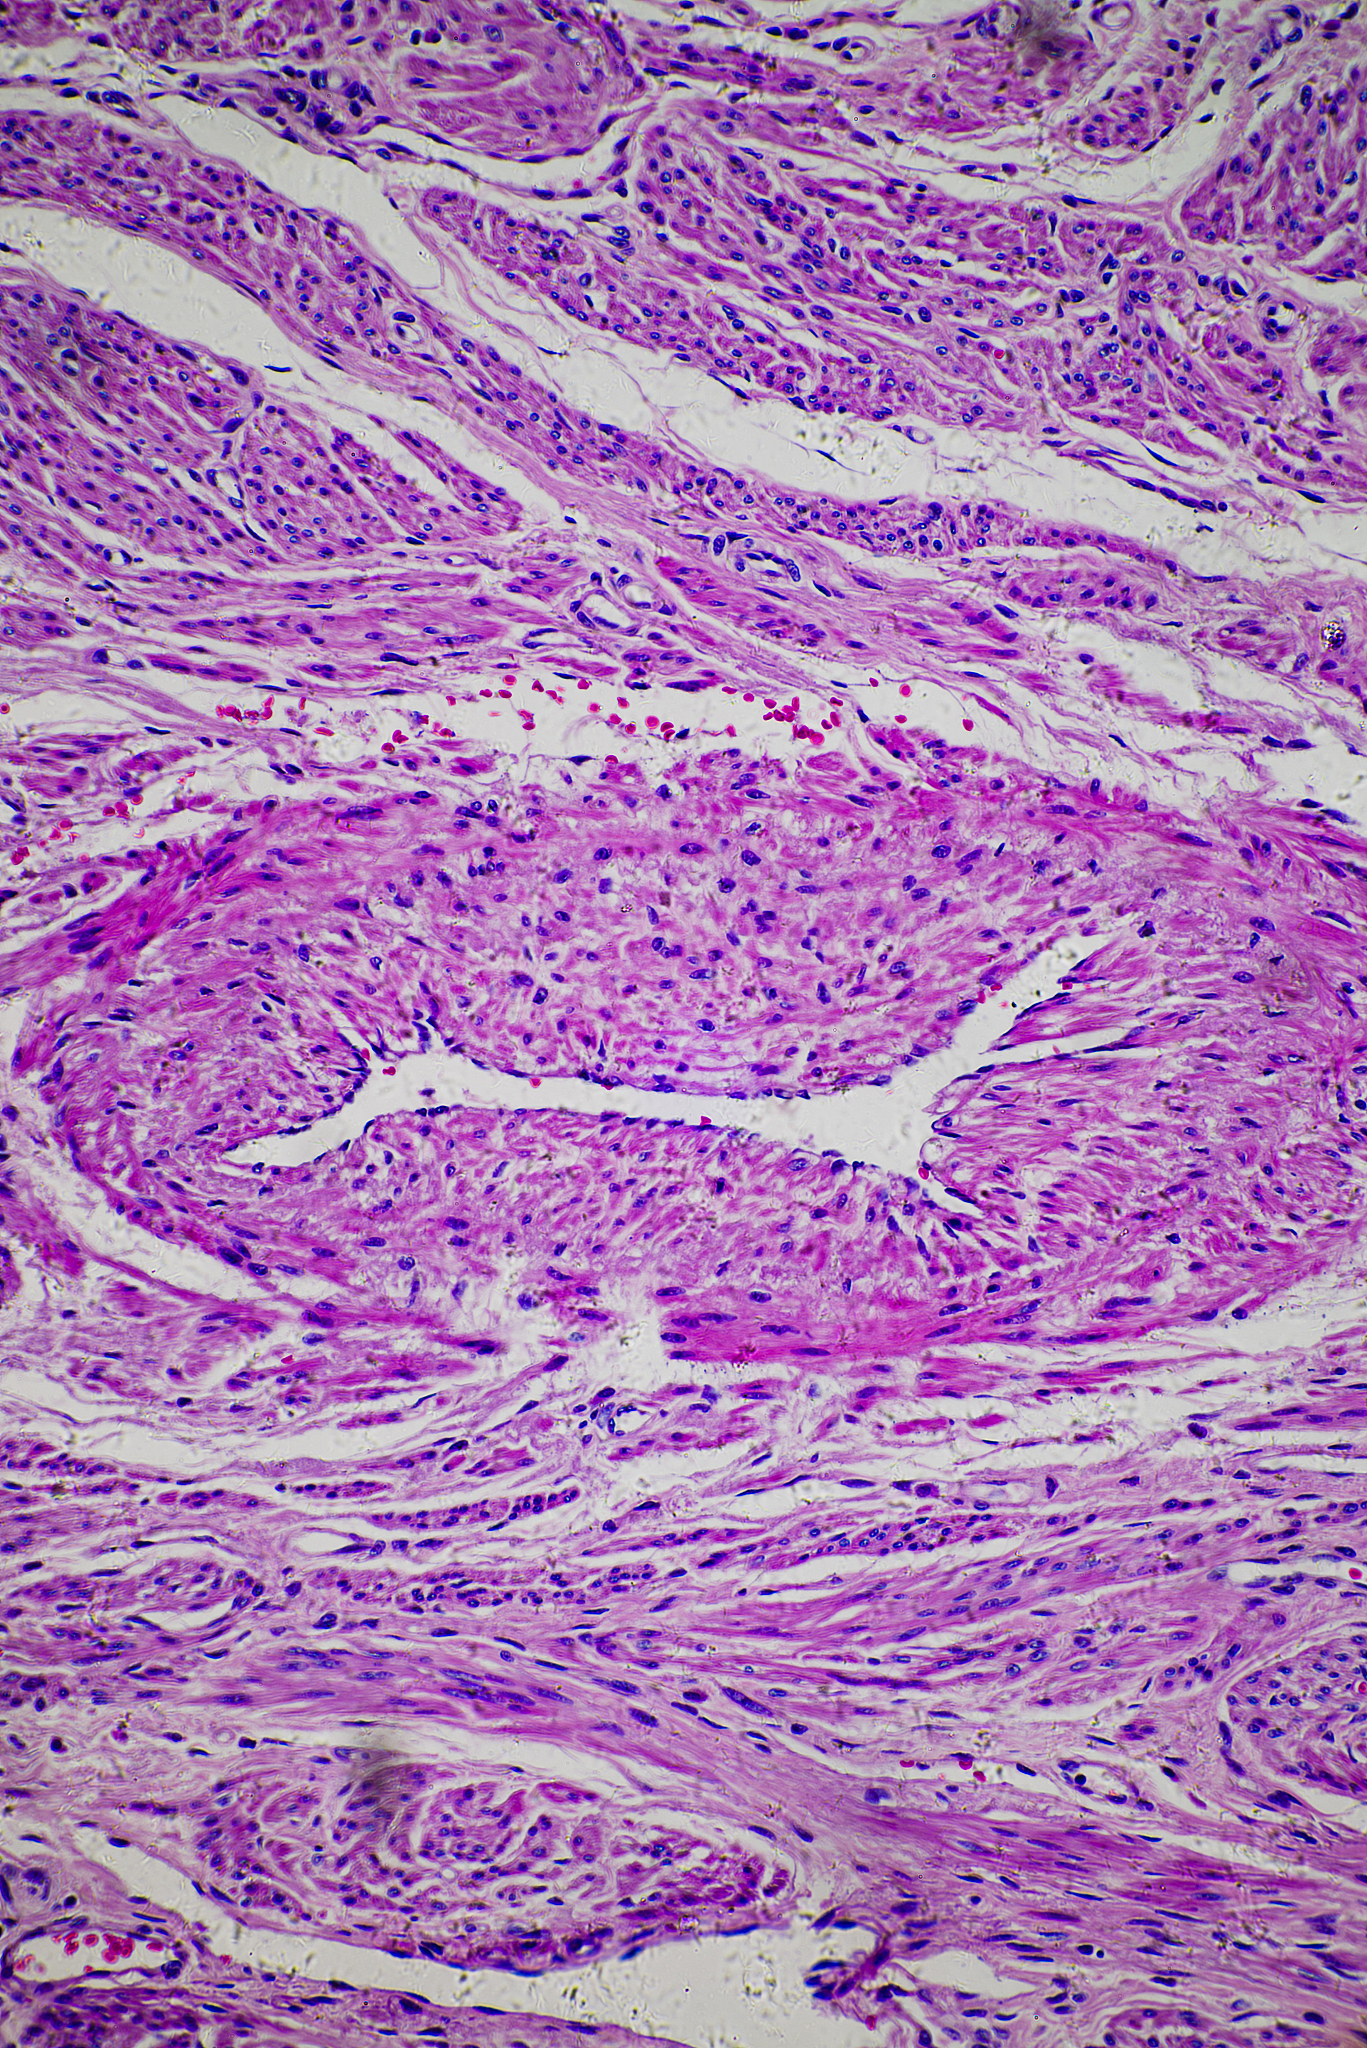

子宫肌瘤是女性常见的妇科肿瘤之一,属于良性肿瘤,是指子宫内膜和肌层中的平滑肌细胞发生良性增生,形成肿块。好发于育龄期女性,尤其是40岁以上的女性。大多数子宫肌瘤没有明显症状,部分女性会出现月经异常、腹部包块、压迫症状等。